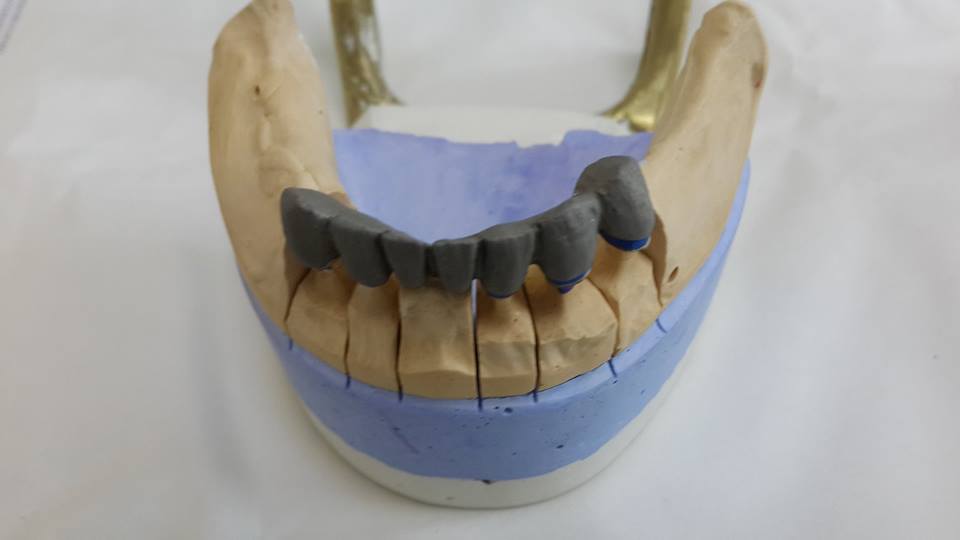

An example of complete rehabilitation of the oral cavity. Treatment included the removal of the old prosthesis, treatment of paradontitis, removal of a large cyst, implantation, clasp prosthesis.